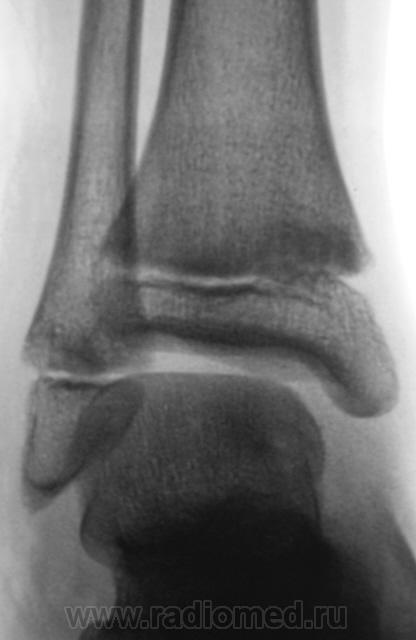

Травма. Пациент направлен хирургом на рентгенографию голеностопного сустава. Произведено стандартное исследование.

Уважаемый Валентин Львович! А что в жалобах, анамнезе? В переднемедиальной зоне дист. метафиза б/берцовой кости субхондрально под зоной роста участок уплотнения к/структуры, не отграниченный от неизмененной костн. ткани. Возможно, это импрессионный перелом? или остеонекроз? Смущает небольшой очаг аналогичной структуры в таранной кости под медиальным валом блока.

Клиника перелома. Травма - за 4 часа до исследования.

Согласен с коллегой helenmar по поводу перелома по типу импрессии, а ещё подвывих стопы в г/стопном суставе.

А как же объяснить асимметрию рентгеновской суставной щели?

А на мой взгляд, суставная щель вполне симметрична.

А, что, это за фрагментик?

1.Fragent.JPG2.Fragent.JPG3.Fragent.JPG

У взрослого такие соотношения в суставе назову супинационным подвывихом, хотя прямая проекция не оптимальна для такого заключения, боковая вовсе косая.

На мой взгляд, все указанные коллегами признаки - не патологические. Травматических повреждений нет.